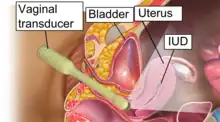

- Ovarian cysts: Enlarged follicles (ovarian cysts) have been diagnosed in about 12% of the subjects using a hormonal IUD in studies that use ultrasound to look for cysts, even if asymptomatic. In studies that only evaluate symptomatic cysts, only 4.5% of women complain of any ovarian cysts over 5 or more years of use, and only 0.3% require IUD removal for ovarian cysts.[54] Thus, any issues with ovarian cysts are not of a clinically relevant nature. Most of these follicles are asymptomatic, although some may be accompanied by pelvic pain or dyspareunia. In most cases the enlarged follicles disappear spontaneously after two to three months. Surgical intervention is not usually required.[55]

- A "lost coil" occurs when the thread cannot be felt by a woman on routine checking and is not seen on speculum examination.[58] Various thread collector devices or simple forceps may then be used to try to grasp the device through the cervix.[59] In the rare cases when this is unsuccessful, an ultrasound scan may be arranged to check the position of the coil and exclude its perforation through into the abdominal cavity or its unrecognised previous expulsion.

Insertion and removal

The hormonal IUD is inserted in a similar procedure to the nonhormonal copper IUD, and can only be inserted by a qualified medical practitioner.[45] Before insertion, a pelvic exam is performed to examine the shape and position of the uterus. A current STI at the time of insertion can increase the risk of pelvic infection.[72] However, routine screening for gonorrhea and chlamydia prior to insertion is not recommended.[73] If a person needs screening and there is no evidence of infection on examination or has been previously screened, insertion of the IUD does not need to be delayed.[74]

During the insertion, the vagina is held open with a speculum, the same device used during a pap smear.[45] A grasping instrument is used to steady the cervix, the length of the uterus is measured for proper insertion with a uterine sound for decreasing chance of uterine perforation with the IUD, and the IUD is placed using a narrow tube through the opening of the cervix into the uterus.[45] A short length of monofilament plastic/nylon string hangs down from the cervix into the vagina. The string allows physicians and patients to check to ensure the IUD is still in place and enables easy removal of the device.[45] Moderate to severe cramping can occur during the procedure, which generally takes five minutes or less. Insertion can be performed immediately postpartum and post-abortion if no infection has occurred.[18]